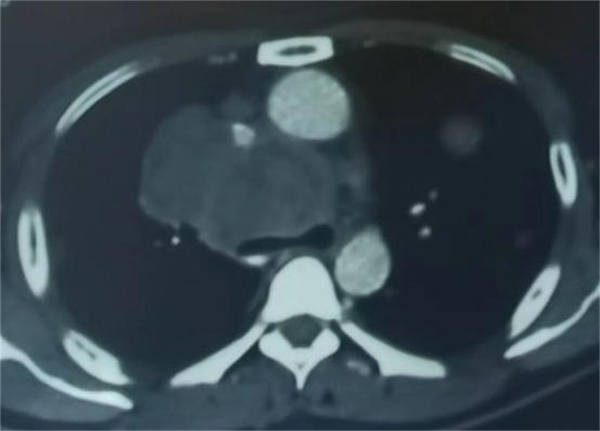

可是,疾病并不会因为疫情来临而退缩,37岁的孙先生患有肝癌,曾经做过肝部分切除术,曾经吃过靶向药物,也做过免疫治疗,但是疾病还是在进展,出现了双肺转移,年轻的孙先生已经备受病痛折磨,可病情仍在加重,出现了憋喘,越来越重,甚至不能平卧,来到应急总医院后,呼吸与危重症医学科医护人员按照防疫流程正常接诊,查胸部CT,发现孙先生的肿瘤压迫气管,气管变窄导致呼吸受阻,需立即手术解除狭窄挽救生命,但是在急诊完善检查,新冠核酸结果还没出来,如果核酸阳性,怎么办?请示周云芝主任,她坚定地说了三个字:“得救命!”这三个字对患者来说是福音!是希望!但对医护团队来说却是重大考验。于是,在院疾控处的协调下,采取最高防护级别,气管镜手术室、麻醉科、手术医生、配台护士、消杀师傅组成了一个有序配合的团队,大家通力合作打响了这台气管镜手术战。

由于占位位于前纵隔,不能平躺麻醉,否则大瘤子就会把气管压迫得更扁更窄,这样无法进行手术。所以只能坐着进行麻醉,然后躺下来,再迅速插入硬质镜,将气管管腔支撑起来,在气管内置入一枚支架,短短25分钟,气管镜室传出喜讯:手术非常成功,患者憋喘症状立刻得到缓解。当患者睁开眼睛那一刹那,家属喜极而泣。看到医护人员站在旁边,患者激动地溢于言表:“谢谢大夫,给了我第二次生命,谢谢!”